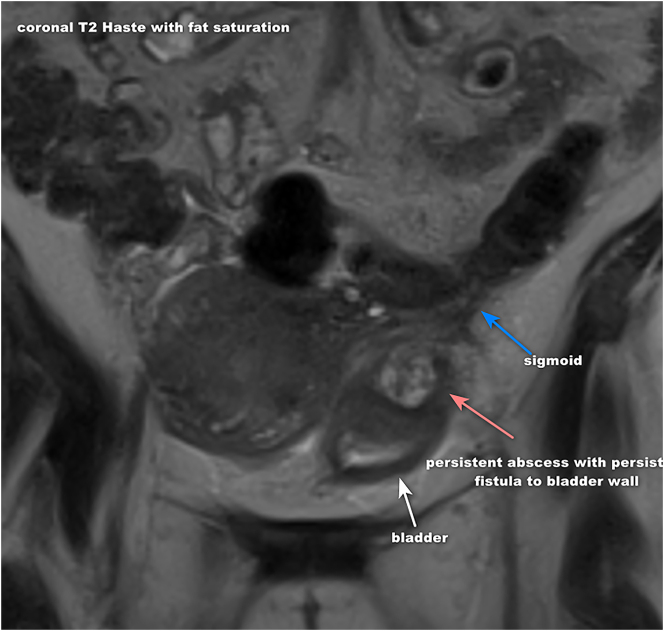

Case presentation: This paper presents a case of a 37-year-old multiparous woman diagnosed with complicated diverticulitis, including colovesical fistula and bladder abscess formation.